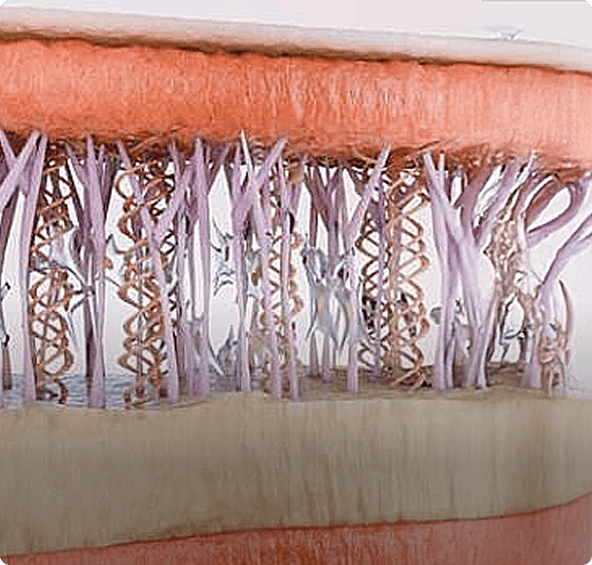

넓고 깊은 LIOB 영역으로

피부조직을 정교하게 컨트롤

스컬피오가 만들어 내는 강력한 에너지와 피코초의 결합은

피부 진피 속 넓고 깊은 영역의 LIOB를 생성해 플라즈마를 발생시킵니다.

피부 깊숙이 전달되는 강력한 에너지

1064PS 핸드피스는 피부 각 층을 정확하게 타게팅 하여 각 층 별 정밀한

에너지 작용으로 피부속 미세 손상을 통해 콜라겐 생성을 촉진합니다.